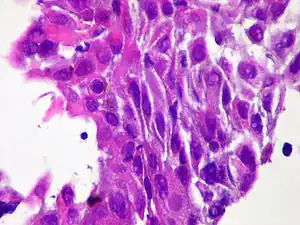

| Micrograph of squamous-cell carcinoma (H&E stain) | |

Squamous epithelial cells are not found in a normal thyroid, so the origin of Squamous-cell carcinoma of the thyroid is not clear. However, it might be derived from embryonic remnants such as thyroglossal ducts or branchial clefts. It is oftendiagnosed in one of the thyroid lobes but not in the pyramidal lobe. Another way it may develop is through the squamous metaplasia of cells. However, that theory is also controversial since Hashimoto's thyroiditis and chronic lymphocytic thyroiditis (neoplasms to be shown squamous metaplasia) are not associated with squamous-cell carcinoma of the thyroid. Primary squamous-cell carcinoma of the thyroid is usually diagnosed in both lobes of the thyroid gland. The histopathology shows a squamous differentiation of tumor cells.